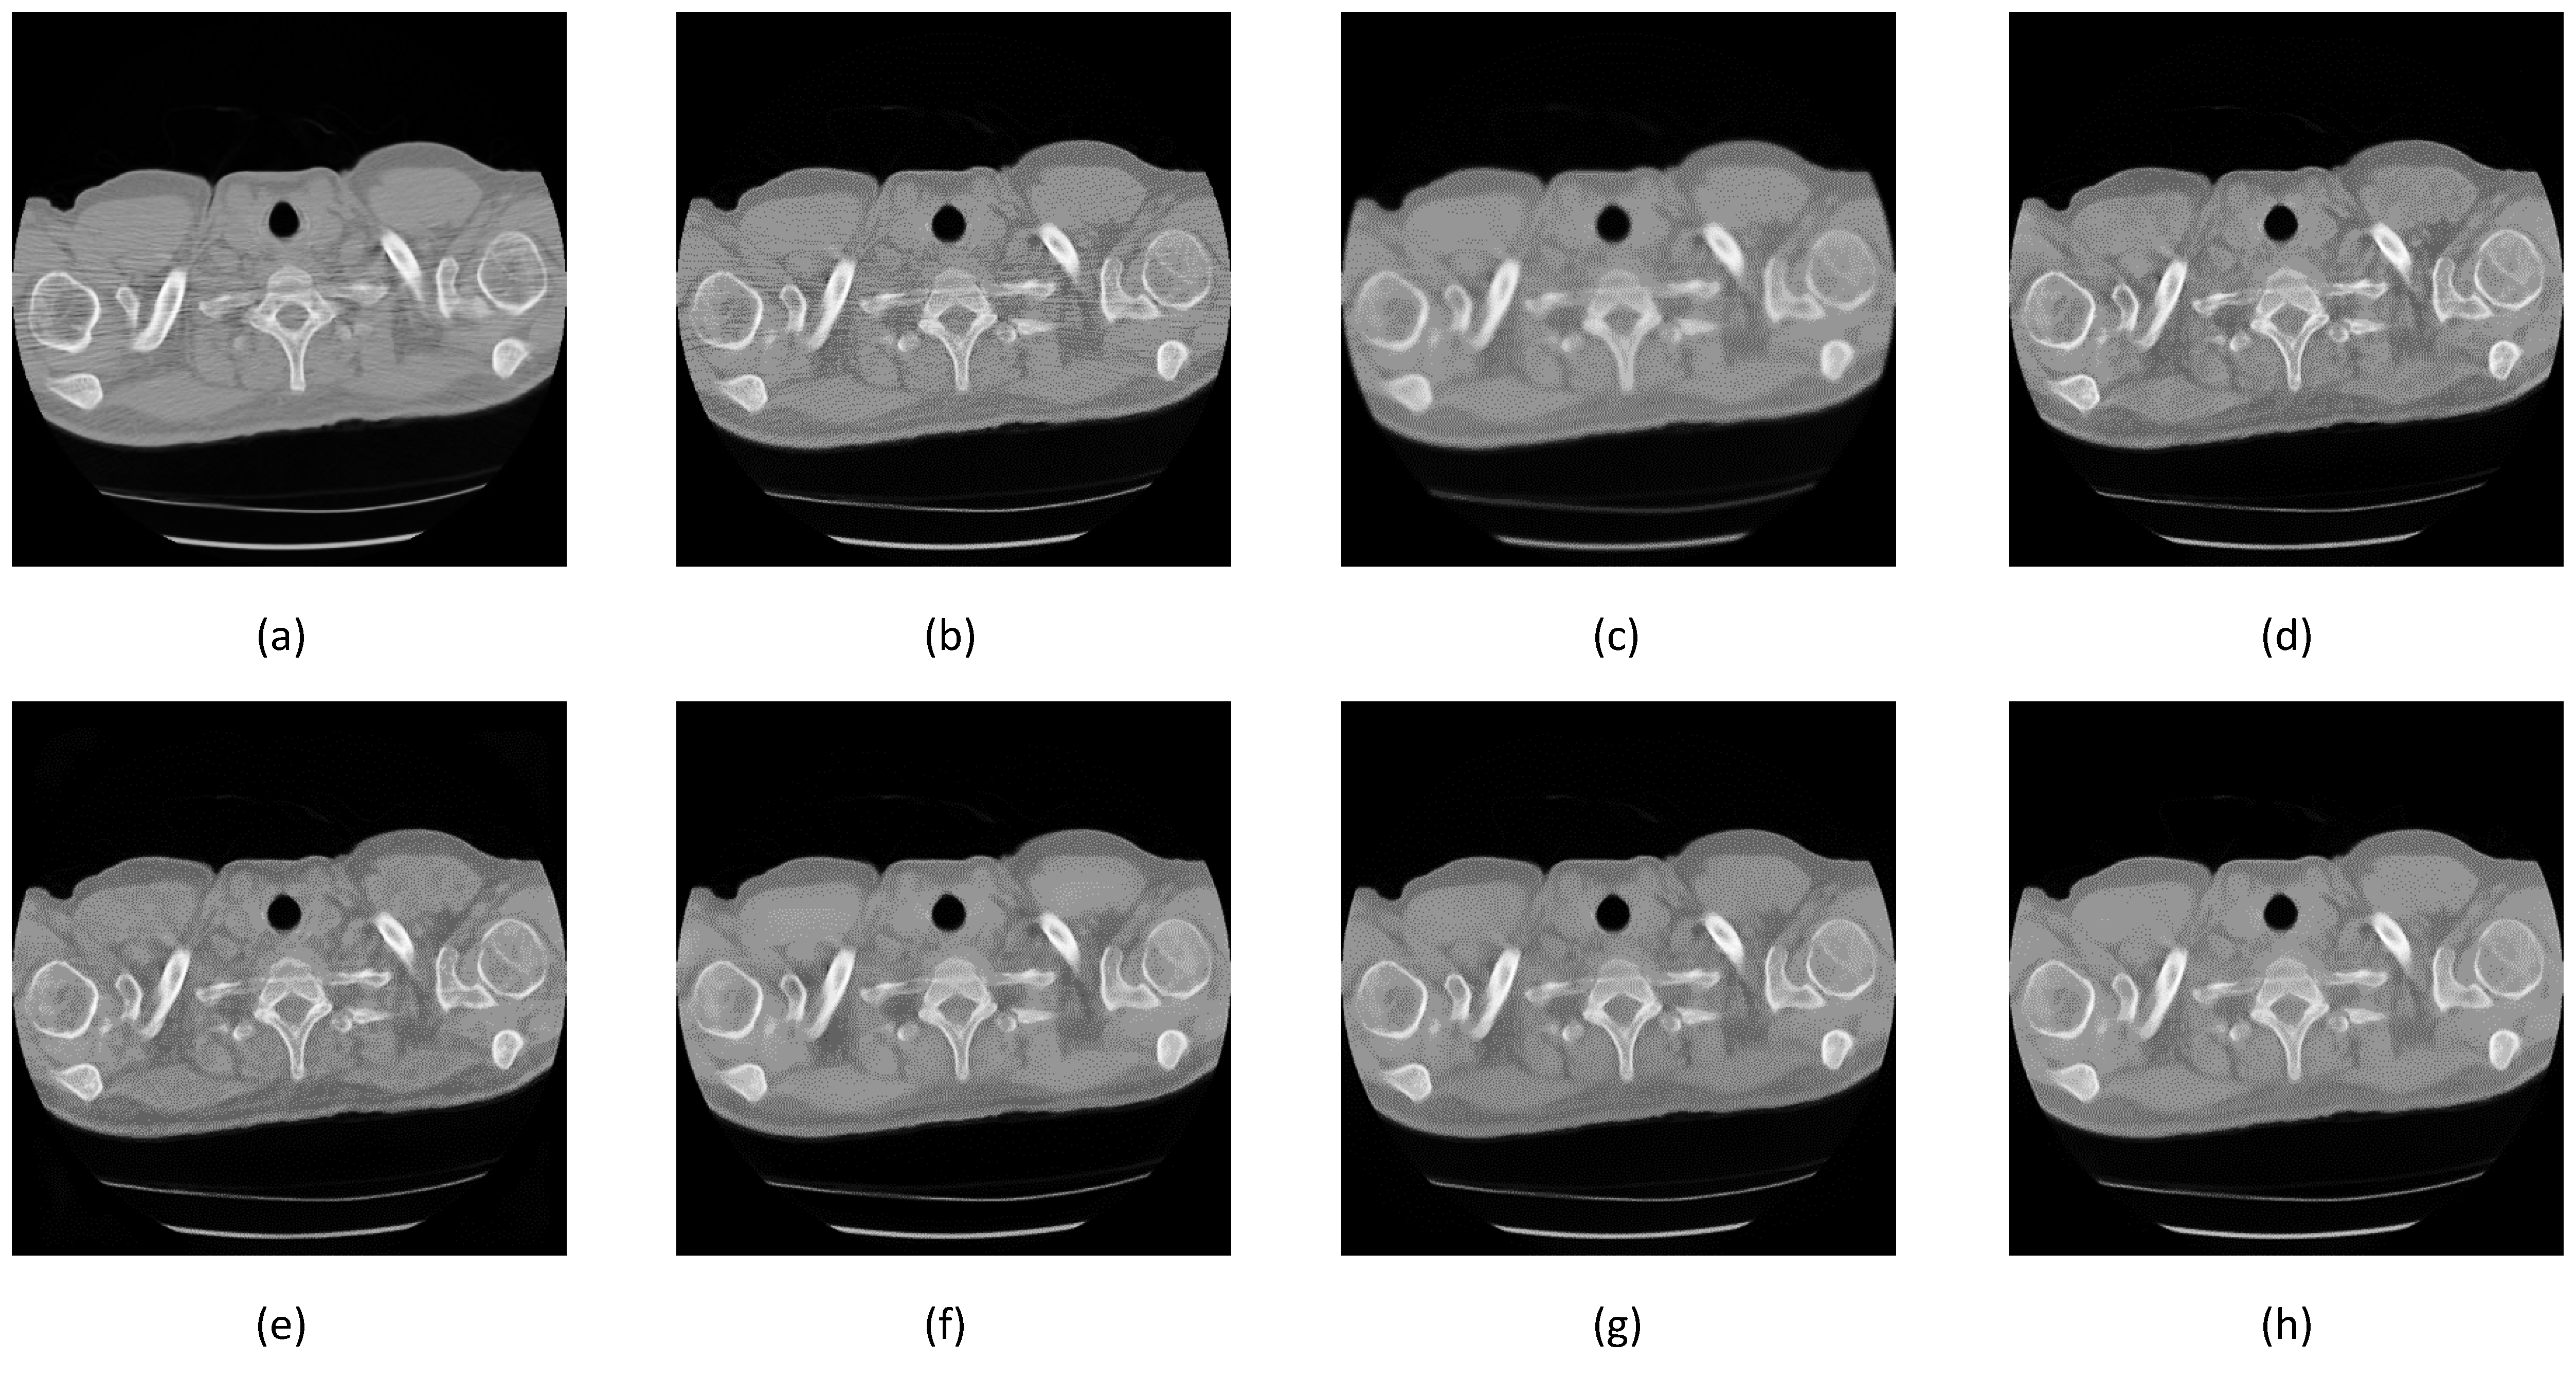

3. Results

3.1. Noise Synthesis

3.3. Comparison between Denoising Techniques